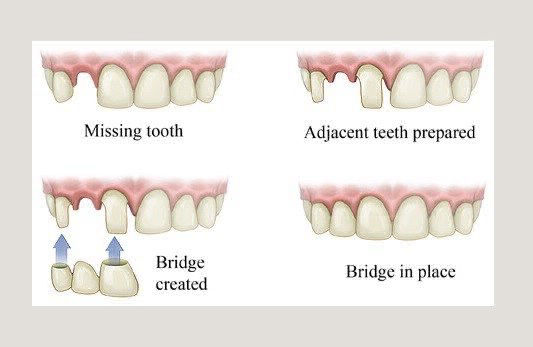

Dental Bridge sering juga disebut dengan jembatan. Gigi tiruan fixed ini dilakukan pada kasus kehilangan gigi yang di sebelah kanan dan kirinya masih terdapat gigi sehat. Jembatan gigi ini memiliki kekurangan yaitu perlunya dilakukan preparasi gigi sebelah kanan dan kiri yang gunanya sebagai penyangga. Kelebihan dari Dental Bridge adalah gigi tiuran ini cekat tidak dilepas pasang sehingga memiliki ketahanan yang lama.